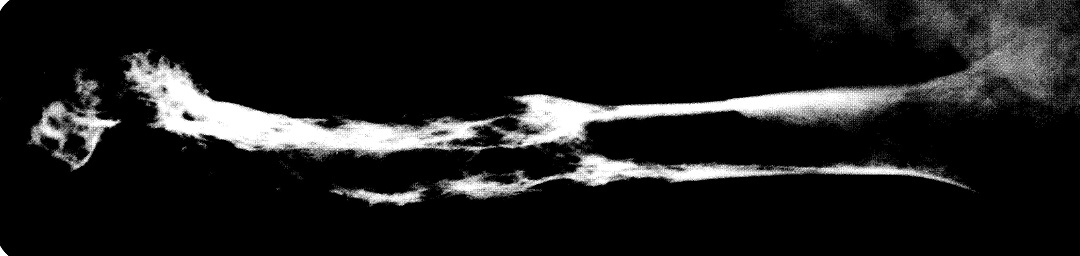

Los cambios radiográficos son patognomónicos, y suelen llevar al diagnóstico. La Fig. 80-2 muestra un húmero; la Fig. 80-3 una vértebra, la Fig. 80-4 una pelvis, y la Fig. 80-5 un cráneo afectados por la enfermedad de Paget; la Fig. 80-6 es el estudio tomográfico del mismo cráneo.

Fig. 80-2. Radiografía de un húmero afectado por la enfermedad de Paget; muestra alteraciones en el extremo distal, con adelgazamiento de la cortical, y áreas alternantes de lucidez y esclerosis.